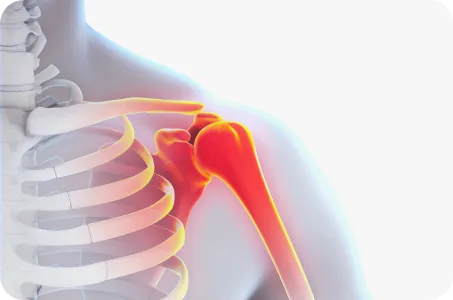

장기 치료 전략견갑골의 위치를 바로잡아, 어깨가 움직일 때 과도하게 사용되는 근육이 없도록 하는 원인 치료

[ 목 X 어깨 X 척추 X 골반 복합치료 ]

어깨로 내려가는 대부분의 신경은 목에서 출발, 경추의 불균형이 있는 경우 이를 교정하여 어깨로 내려가는 신경이 압박받지 않도록 공간 확보가 필수적

척추

굽은 등과 편평등은 견갑골의 위치를 틀어지게 만드는 주범으로 등뼈가 정상적인 커브를 이루고 있을 때 어깨가 가장 편하고 바른 자세가 됨

골반

어깨를 아래로 잡아주는 광배근, 중하부승모근은 골반이 틀어지거나, 양쪽 골반 높이가 다르면 어깨도 함께 틀어질 수 밖에 없음